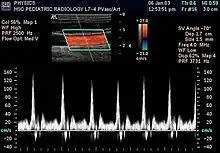

- Modo Doppler: Este modo hace uso del efecto Doppler, para visualizar el flujo sanguíneo.

- Doppler color: La información sobre la velocidad y dirección del flujo en tiempo real se representa con unidades de color.[23]

- Doppler espectral: En vez de utilizar colores, muestra la circulación de la sangre en un gráfico. Se puede utilizar para mostrar el nivel de bloqueo de un vaso sanguíneo.[23]

La ecografía doppler o simplemente eco-Doppler es una variedad de la ecografía tradicional, basada por tanto en el empleo de ultrasonidos, en la que aprovechando el efecto Doppler, es posible visualizar las ondas de velocidad del flujo que atraviesa ciertas estructuras del cuerpo, por lo general vasos sanguíneos, y que son inaccesibles a la visión directa.[24] La técnica permite determinar si el flujo se dirige hacia la sonda o si se aleja de ella, así como la velocidad de dicho flujo. Mediante el cálculo de la variación en la frecuencia del volumen de una muestra en particular, por ejemplo, el de un flujo de sangre en una válvula del corazón, se puede determinar y visualizar su velocidad y dirección. La impresión de una ecografía tradicional combinada con una ecografía Doppler se conoce como ecografía dúplex.[1]

La información Doppler se representa gráficamente con un Doppler espectral, o bien como una imagen usando Doppler direccional o un power Doppler (Doppler no-direccional). La frecuencia Doppler cae en el rango audible y puede escucharse utilizando altavoces estéreo, produciendo un sonido pulsátil distintivo.